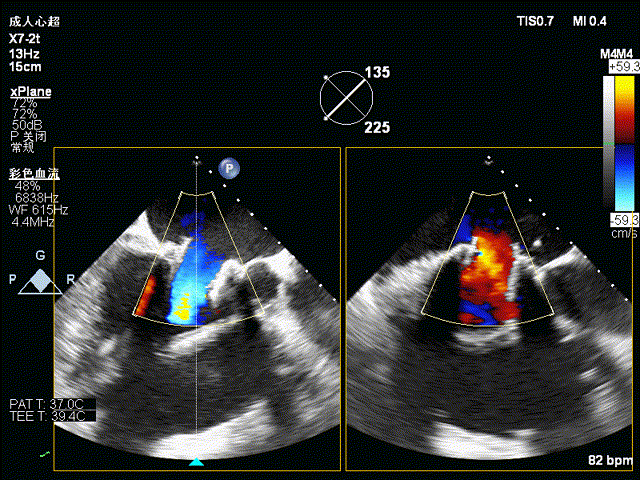

术前食道超声示:

术前食道超声